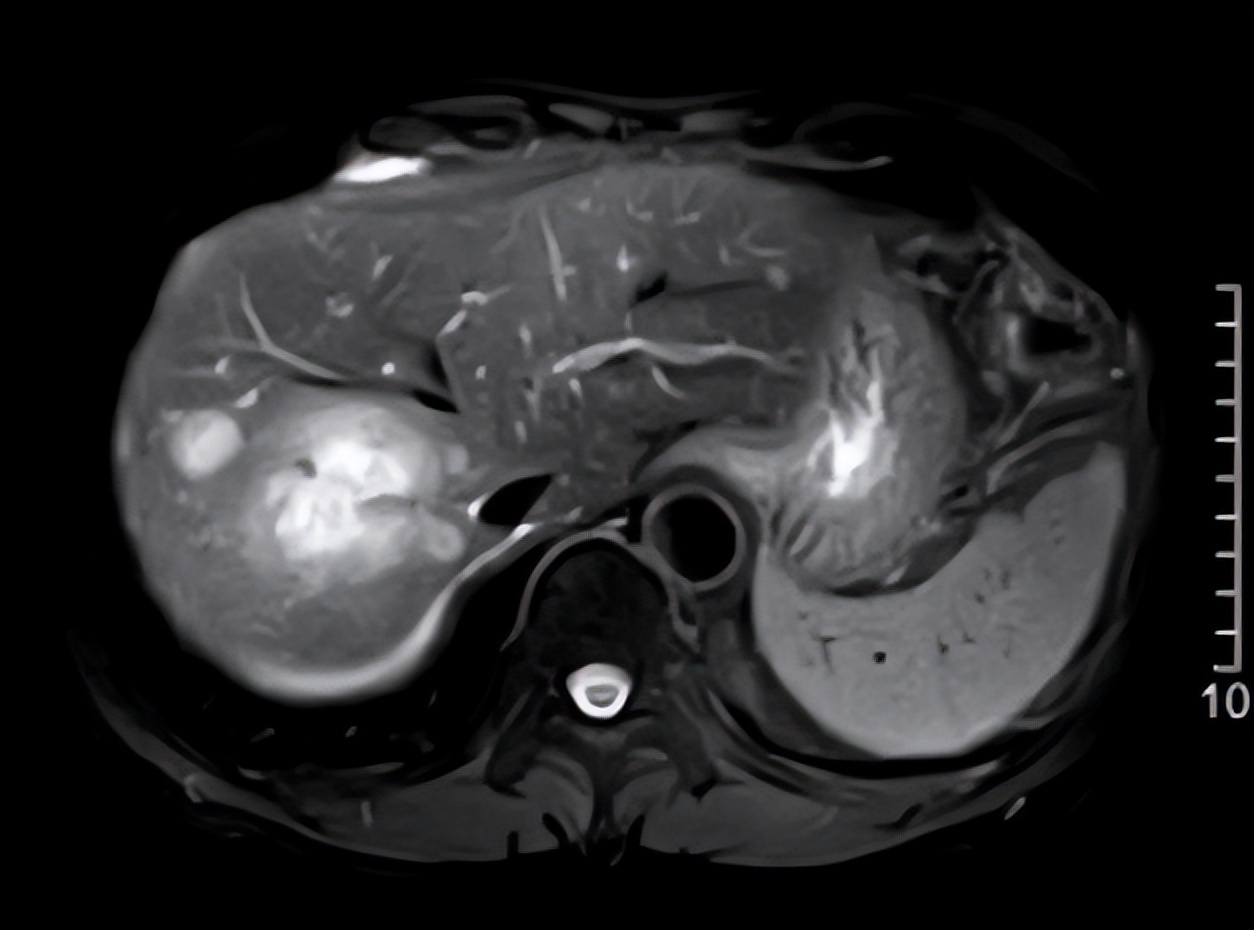

△2020年11月10日MRI

△治疗前后影像(MRI)对比:2020年11月10日MRI(上)vs.2021年11月16日MRI(下)